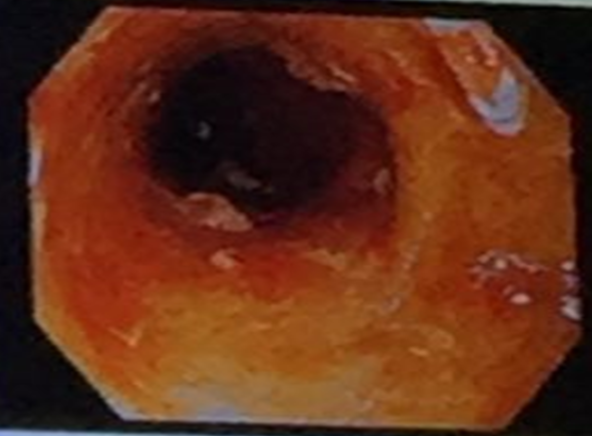

Crohnâs Disease

What is observed in the X-ray? Cobblestone appearance. What is the likely diagnosis? Crohnâs disease.